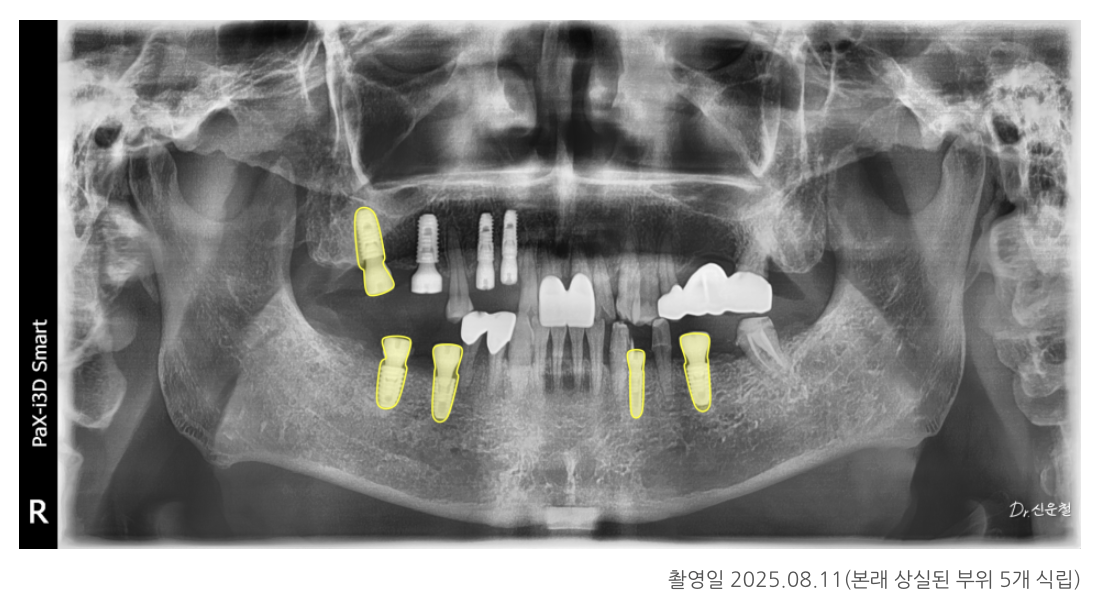

1단계: 상실된 치아 부위 임플란트 식립

임플란트는 단순히 ‘빠진 이를 채우는 것’이 아니라

무너진 씹는 힘의 균형을 다시 잡는 기둥 역할을 합니다.

치아가 빠진 상태로 오래 방치되면

반대편 치아는 내려오고

양옆 치아는 빈 공간 쪽으로 기울면서

전체 교합이 망가집니다.

환자분은 총 5개 부위에 임플란트를 먼저 식립했습니다.

최종 결과: 전체 균형을 다시 회복

임플란트와 보철 치료가 모두 자리 잡은 뒤

다시 촬영한 사진에서는

✓ 양쪽으로 균형 있게 씹을 수 있는 교합

✓ 앞니·어금니의 힘 분산 안정

✓ 정출·기울기 문제 해결

이 확인되었습니다.